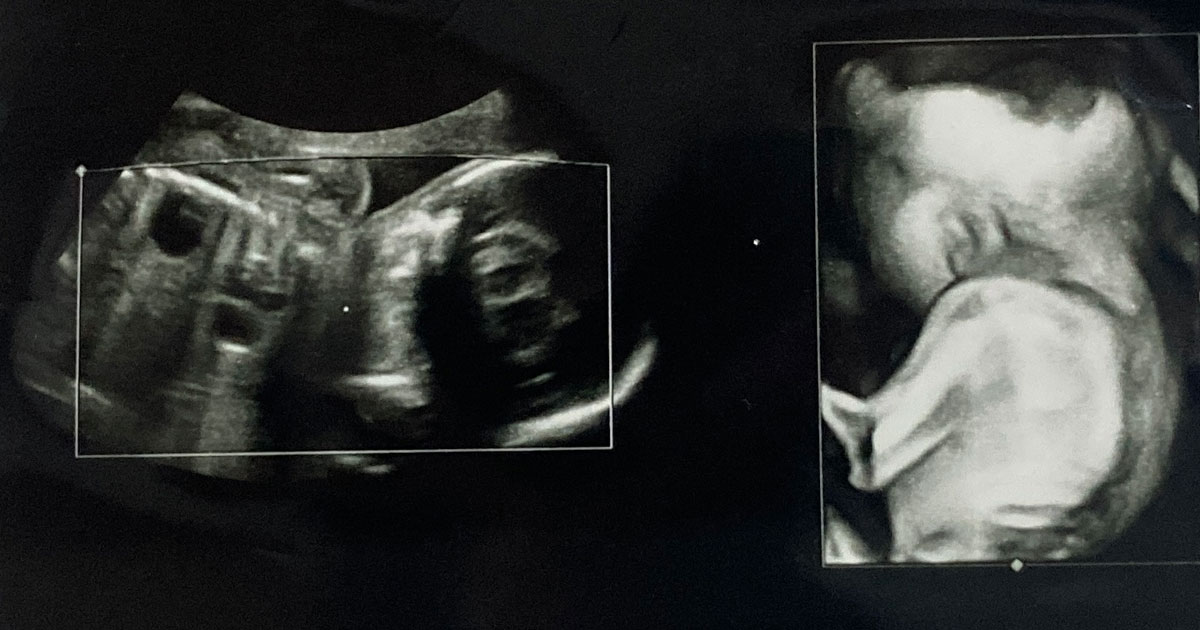

医療専門家は、妊娠中期のスキャン中に二分脊椎症を診断することがよくあります。通常、この検査は妊娠 18 週から 21 週の間に実施されます。場合によっては、医師が出生後に二分脊椎症と診断することがあります。